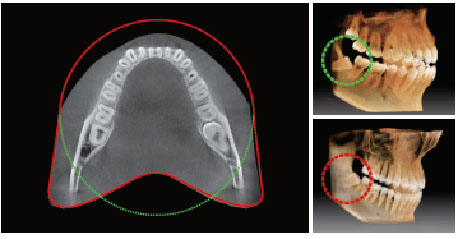

FOV 12x9 Anatomic

Inovaţia FOV a Pax-i3d Smart oferă un volum în formă de arc, care prezintă o vedere mai largă a arcadei în comparaţie cu alte dispozitive din acelaşi FOV.

În mod normal, o imagine 10x8.5 FOV achiziţionează inclusiv molarul 3. Cu toate acestea, atunci când dintele este poziţionat anormal, există o mare posibilitate ca acesta să fie tăiat din imagine.

"Volumul în formă de arc" elimină această posibilitate şi arată întreaga arcadă, bimaxilară.